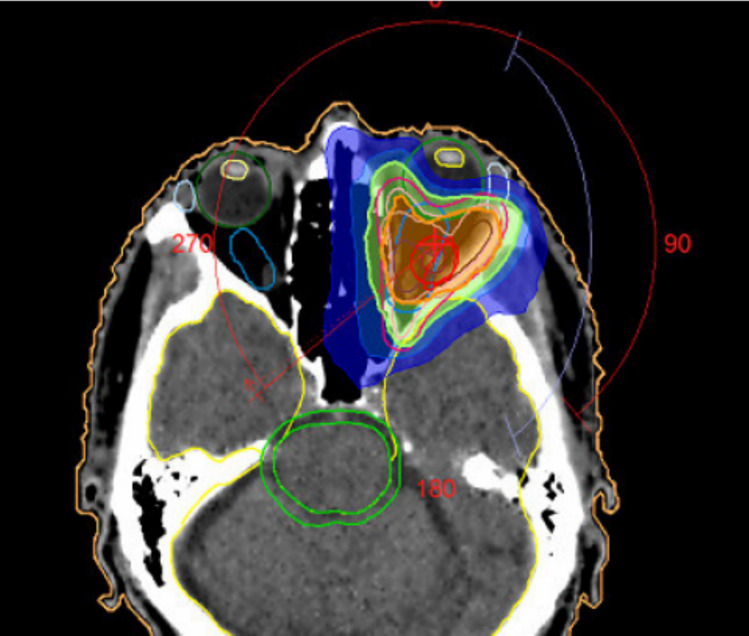

我们报道了一名复发性转移性头颈部鳞状细胞癌(HNSCC)和程序性死亡配体1 (PD-L1)阴性表达的患者对免疫检查点抑制剂nivolumab联合局部热疗(RHT)的长期反应。治疗耐受性良好,无局部副作用。在纳武单抗和RHT治疗下,眼眶和咀嚼区肿瘤相关症状逐渐减轻。在治疗过程中,磁共振成像(MRI)显示在加热的肿瘤区域局部肿瘤得到控制,而转移性病变发生在RHT区以外的区域。这是第一个病例报告,证明了在这种预后不佳且对免疫检查点抑制剂反应率低的患者群体中添加RHT的可行性和临床潜力。RHT可能是激活对免疫检查点抑制剂有反应的免疫原性环境的另一种工具。

We report a long-lasting response to the immune checkpoint inhibitor nivolumab in combination with regional hyperthermia (RHT) in a patient with recurrent metastatic Head and Neck Squamous Cell Carcinoma (HNSCC) and negative programmed death ligand 1 (PD-L1) expression. Treatment was well tolerated with no local side effects. Tumor-related symptoms in the orbital and masticator area gradually decreased under treatment with nivolumab and RHT. Over the course of treatment, magnetic resonance imaging (MRI) showed a local tumor control in the heated tumor areas, while metastatic lesions developed in areas outside of the RHT field. This is the first case report demonstrating the feasibility and clinical potential of the addition of RHT in this patient collective with poor outcomes and low response rates to immune checkpoint inhibitors. RHT might be an additional tool to activate an immunogenic milieu responsive to immune checkpoint inhibitors.